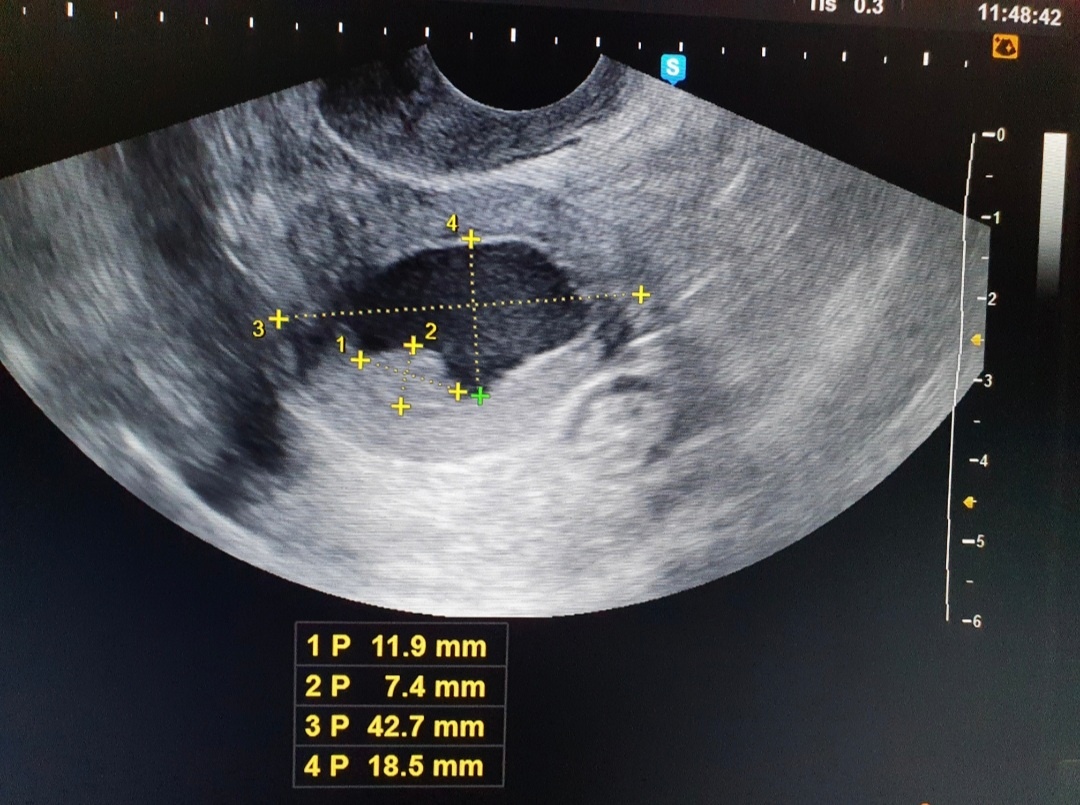

И по УЗИ выявлена вот такая картина.

Фото из личного архива.  На фото - тело и шейка матки .

На фото можно увидеть расширение полости матки до 18 мм, полость заполнена жидкостью, более вероятно слизью ( серозометра).

И по задней стенке мы видим дополнительные образования ( полипы или очаговая гиперплазия эндометрия).

Кровоток в данном образовании достоверно не определяется.

Настораживает тот факт, что год назад этого не было ( протокол УЗИ я видела, смотрел хороший доктор, которому можно доверять). И настораживает значительное расширение полости за счёт серозометры. Это считается неблагоприятным признаком.